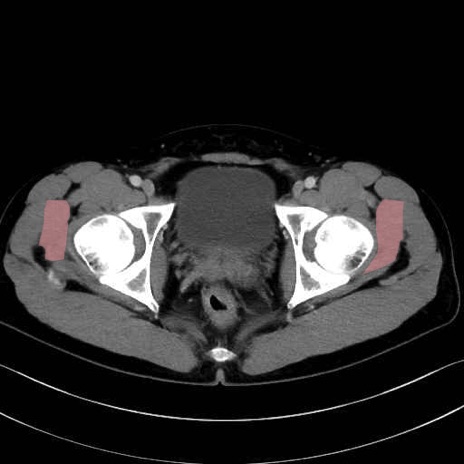

小殿筋 (Gluteus minimus)